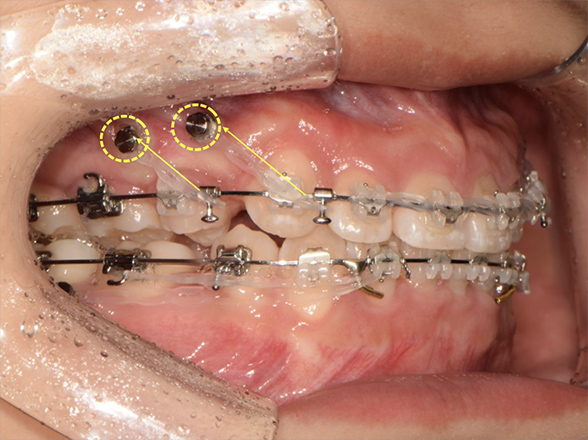

Total Arch Intrusion (전치열 함입)